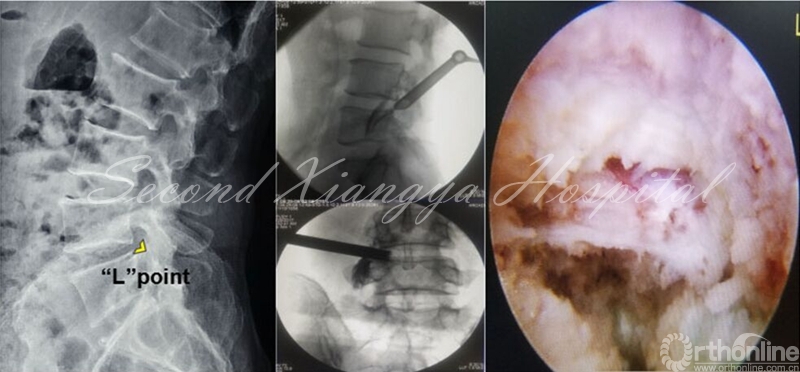

虽然上述三种技术有所不同,但术中定位均以骨性结构“L”点为标志是其共同特点。“L”点指的是上关节突基底部与椎体后上缘交接区,以此点来建立工作通道可以有效避开神经与血管结构,同时通过关节突成型扩大操作空间,从而完成安全减压操作。

椎间孔入路操作技巧应注意“关突引导,循骨而进,成型忌粗,遇痛即止。”也就是说,以上关节突为引导,沿着上关节突进入到硬膜外间隙,固定通道后,探及底面为硬性骨组织后,用环锯进行一次成型,成型后半过程如患者出现神经疼痛,应停止前进,术中并用透视证实成型工具末端不超过椎弓根内侧缘。